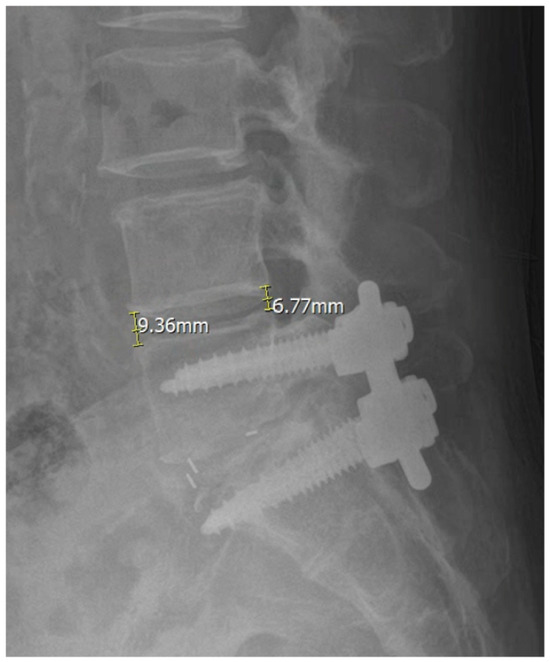

3.5. Illustrative Case

We present the case of an 80-year-old female who developed symptomatic cranial adjacent segment degeneration at L3–4 following posterior lumbar interbody fusion at L4–5, performed 4 years ago. Her primary complaint was progressive right anterior thigh pain. Preoperative pain assessment revealed VAS scores of 8 for back pain and 7 for leg pain. Standing radiographs showed decreased disk height at L3–4 with maintained alignment at the previously fused L4–5 segment. MRI demonstrated severe disk degeneration at L3–4 with central canal and bilateral foraminal stenosis.

The patient underwent PSP-LLIF at L3–4 with supplemental posterior instrumentation extending from L3 to L5, incorporating the L3–4 level into the existing fusion construct. The entire procedure was completed in 110 min without position change. Intraoperative fluoroscopy confirmed appropriate cage positioning. At 12-month follow-up, VAS scores improved to 3 for back pain and 2 for leg pain. Radiological measurements showed LL increased from 27.87 degrees to 36.94 degrees, SL increased from 6.16 degrees to 15.99 degrees, ADH increased from 7.03 mm to 12.87 mm, and PDH increased from 5.85 to 9.39 (Figure 2). Dynamic radiographs confirmed solid fusion without evidence of hardware loosening, cage subsidence, or migration.

Figure 2. Anteroposterior (AP) and lateral radiographs before and after surgery in a representative case of prone single-position lateral lumbar interbody fusion (PSP-LLIF). (A,B) Preoperative and (C,D) 12-month postoperative AP and lateral standing radiographs of an 80-year-old female following PSP-LLIF at L3–4 with supplemental posterior instrumentation from L3 to L5. Postoperative radiographs demonstrate restored L3–4 disk height, increased lumbar lordosis (LL) and segmental lordosis (SL), and improvement in anterior disk height (ADH) and posterior disk height (PDH), with confirmed fusion and no evidence of hardware loosening, cage subsidence, or migration at 12 months.